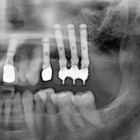

L’implantologia include anche alcune procedure chirurgiche avanzate che creano le condizioni per la risoluzione dei casi più difficili e per la semplificazione di alcune fasi degli interventi.

RIALZO DEL SENO MASCELLARE

INNESTI OSSEI